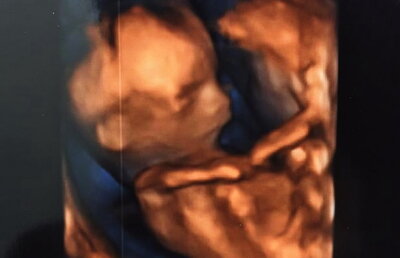

Ea este cea mai sexy graviduţă a momentului! Va avea o fetiţă